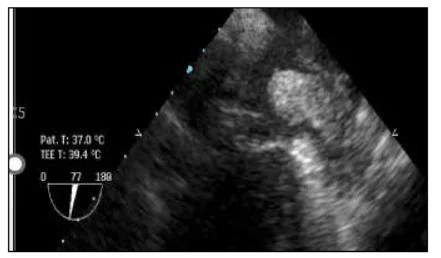

На початку дослідження за даними трЕхоКГ практично у кожного третього (34,7%)із 49 учасників, які готувалися для проведення планової ЕКВ, були виявлені тромб ВЛП (22,5%) та ФСК 4+ (12,2%). Частота появи тромбу ВЛП (рис. 3) становила 22,4% (n=11), що співпадає із даними інших випробувань, де вона коливалася від 1,2 до 22,6%, причому значна варіація показника залежала від декількох клінічних і гемодинамічних факторів, а саме тривалості й форми ФП, супутніх факторів ризику (CHA2DS2-VA), гемодинамічних та анатомічних чинників, комплаєнсу при проведенні АКТ. Висока частота виявлення тромбоутворення та ФСК 4+ у дослідженні, що розглядається, підкреслює необхідність проведення максимально ефективних діагностичних підходів (трЕхоКГ чи комп’ютерної томографії) в алгоритмі підготовки пацієнта із персистуючою формою ФП до планового відновлення синусового ритму шляхом ЕКВ.

Рис. 3. Тромб ВЛП